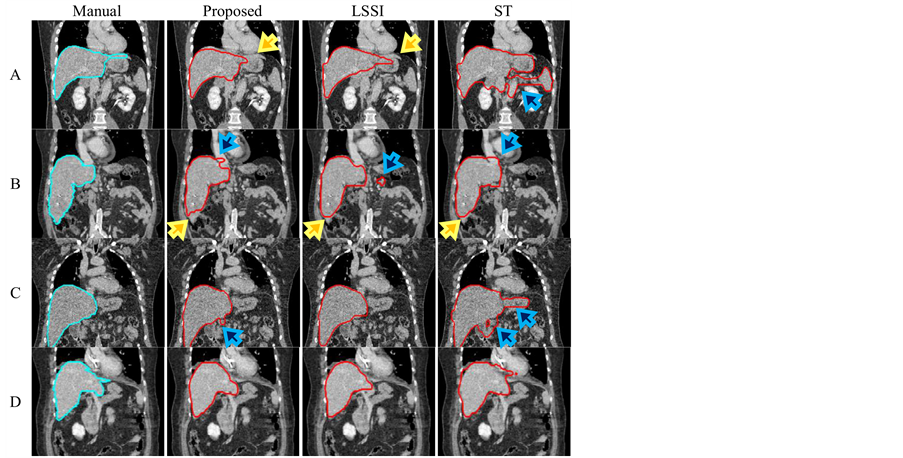

Next, Figure 9 shows examples of liver’s boundaries in coronal and sagittal images. The under-segmentation was a major problem of the proposed method as indicated by yellow arrows. This problem arises when an initial process creates extremely small seed-regions. Next, the results of liver segmentation based on the LSSI technique contained over or under-segmentations when some boundaries of anatomical structures were not extracted well in the speed images. Moreover, a critical problem of liver segmentation based on the ST technique is to cause a kind of over-segmentation as shown by blue arrows. In our opinion, this problem occurs when data sets include large variation in averages of gray-intensities among different axial-images. Further, sizes and locations of seed regions used in statistical measures occasionally fail to give good approximate liver’s regions.

Figure 9. Eight examples of liver-segmentation results: (Top) outlines in coronal images, and (bottom) outlines in sagittal images. The results show at slice 160 in patient A (phase 70), B (phase 30), C (phase 50), and D (phase 90).